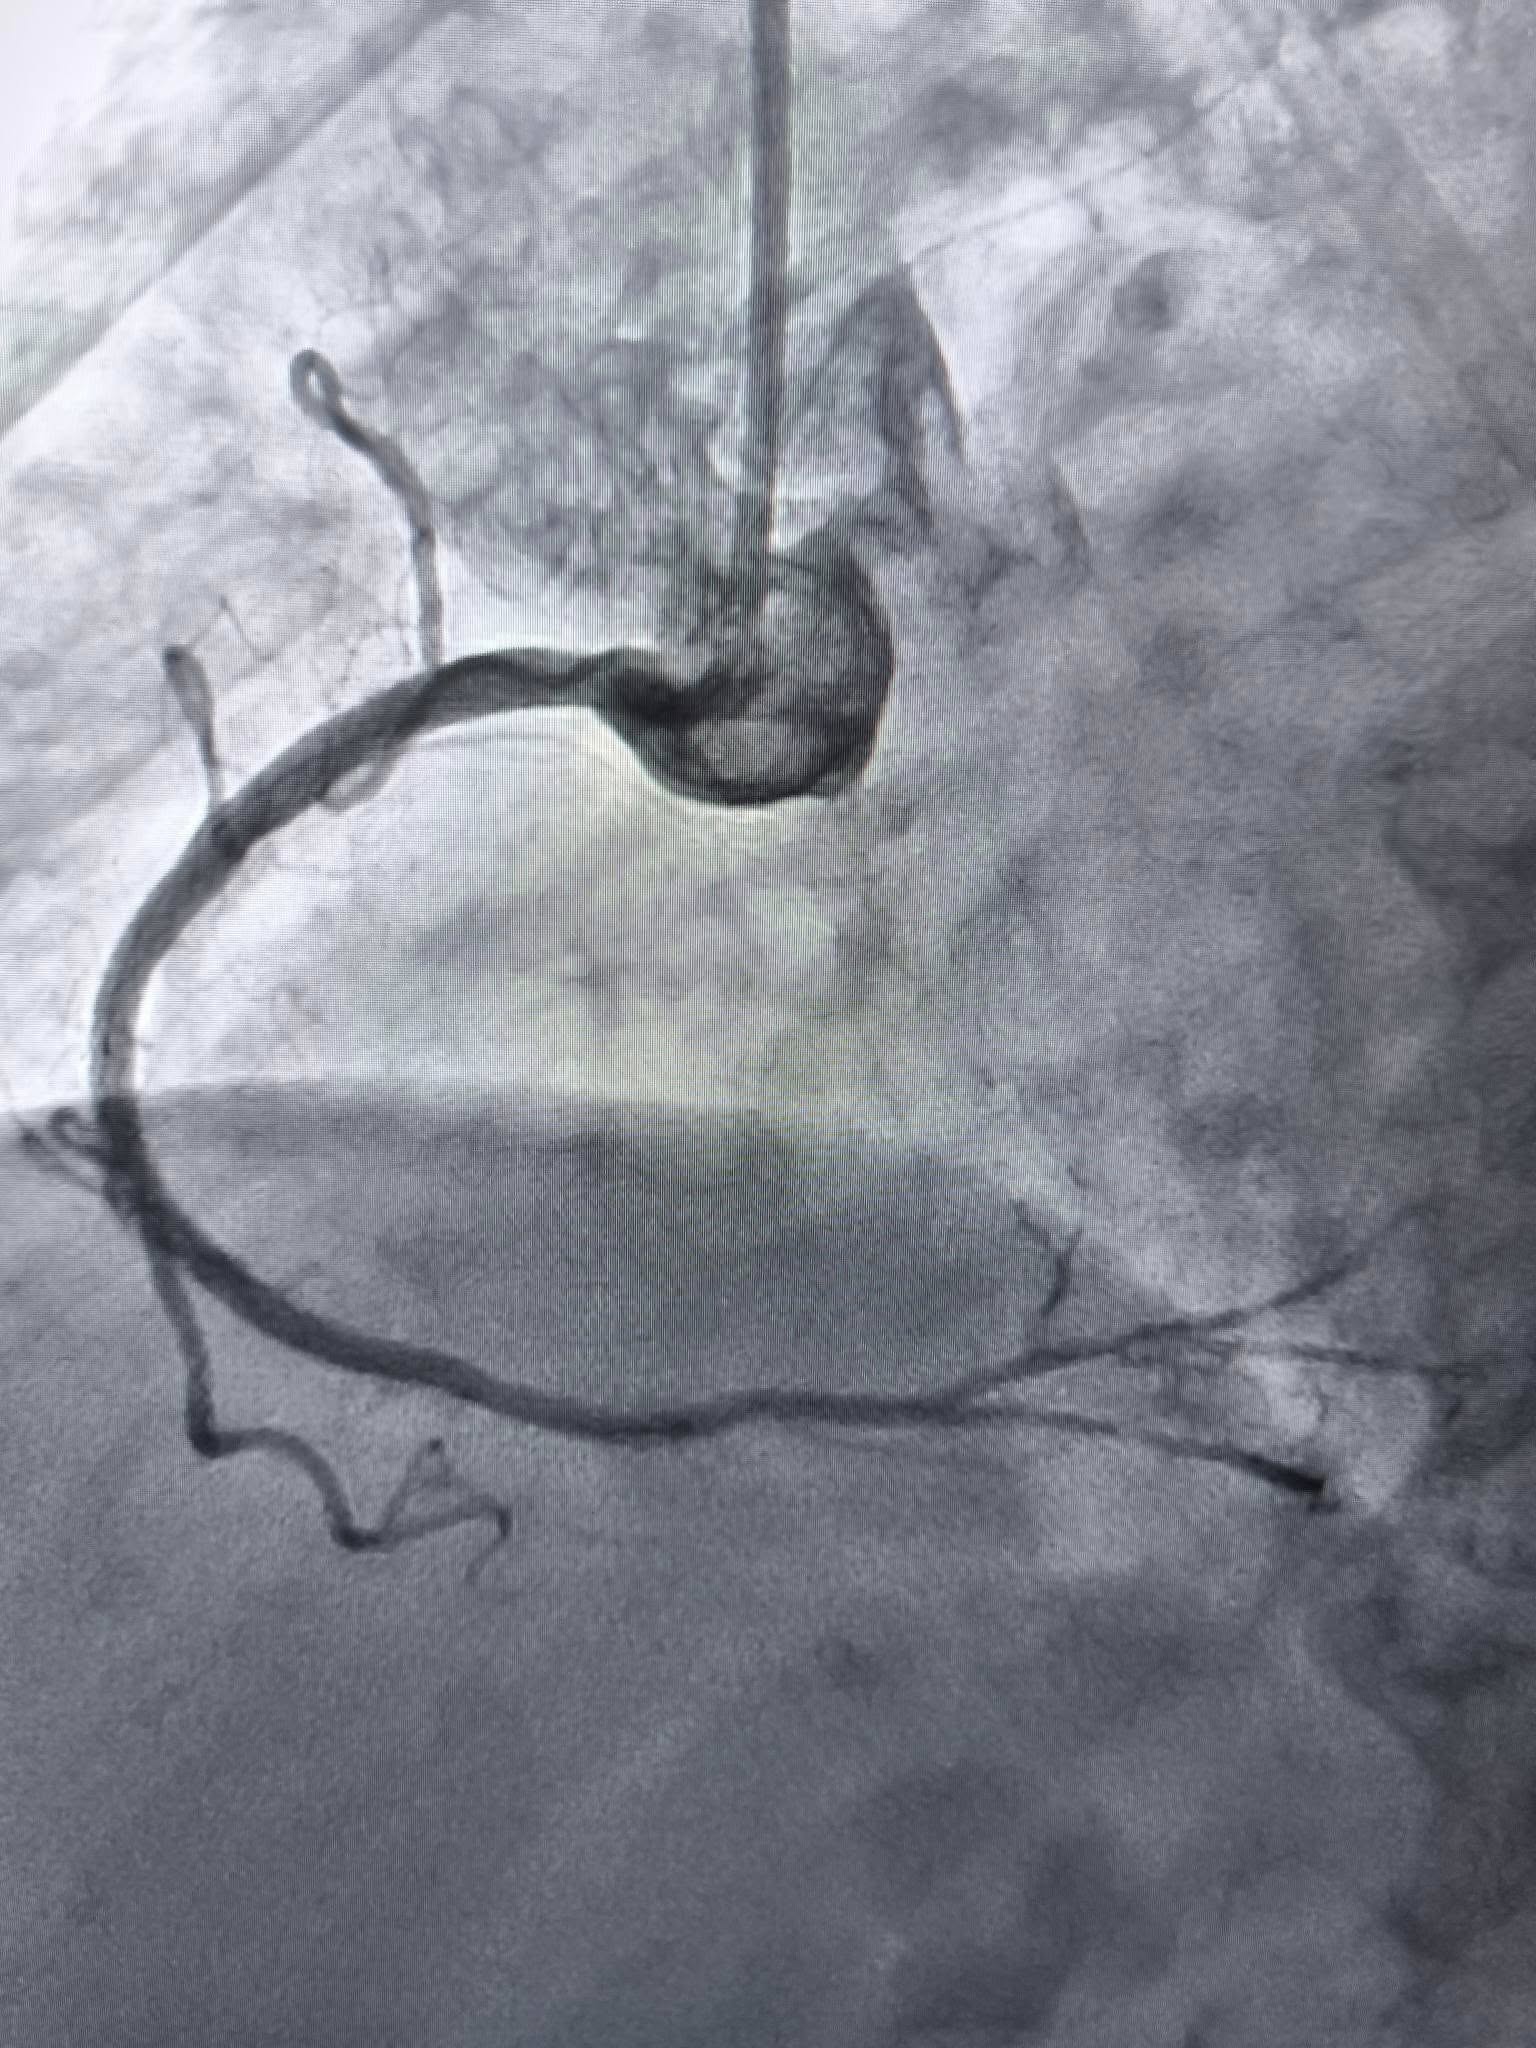

За словами завідувача відділенням інтервенційної радіології, кардіології та реперфузійної терапії Богдана Маслія, у пацієнтки діагностували значне звуження правої коронарної артерії.

Розширити її традиційним способом – шляхом роздування балона, не вдалося, навіть із використанням балона високого тиску до 25 атмосфер (це приблизно у десять разів більше, ніж тиск в автомобільному колесі).

Саме таким методом лікарям вдалося ліквідувати перешкоду в артерії та успішно імплантувати стенти.